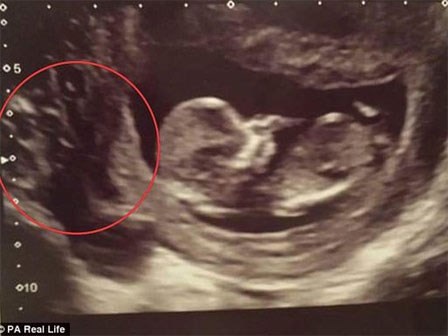

Siêu âm thai 12 tuần, mẹ bầu khóc nức nở khi thấy nhau thai rỗ như tổ ong

Tưởng rằng bản thân mình bị mang thai trứng, mẹ 30 tuổi sẵn sàng mạo hiểm tính mạng để giữ lại con gái của mình trước khi phát hiện ra vấn đề thực sự mà mình gặp phải.